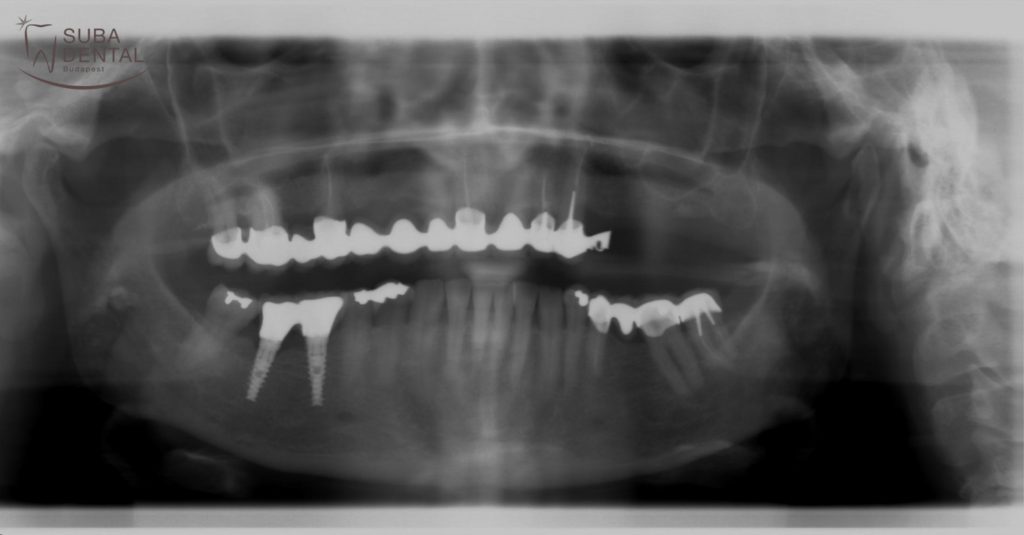

Az első konzultáció alkalmával a panorámaröntgen alapján alaposan megvizsgáltuk a fogak állapotát. CBCT (Cone beam computed tomography) felvétel alapján pontosan láthatóvá vált, hogy a csontkínálat megfelelő ahhoz, hogy az hiányzó jobb alsó őrlőket implantátumokkal pótoljuk. A bal felső régióban viszont az implantátumokkal való pótlás csak csontpótlással (sinus lift) lehetséges, melyet páciensünk nem szeretett volna.

Panoráma röntgen, melyet a páciens hozott magára az első konzultációra